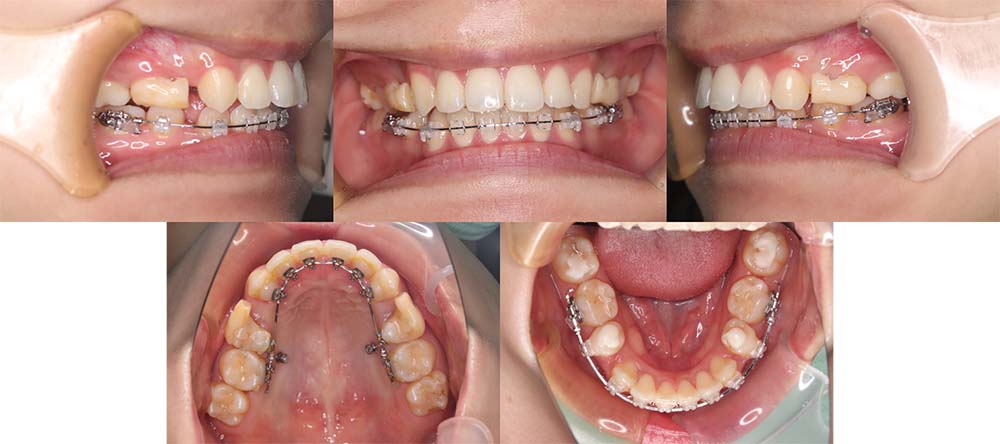

| 症例分類 | 上顎前突、叢生、シザースバイト |

| 診断名 | 右上7のシザーズバイトを伴う上下重度叢生skeletal2 |

| 主訴 | 歯並びが悪くて全体的にガタガタ |

| 年齢 | 19歳11ヶ月 |

| 性別 | 女性 |

| 抜歯部位 | 上顎左右と右下の第一小臼歯、左下の第二小臼歯(4本)、上顎右側第二大臼歯 |

| 使用装置 | 裏側のワイヤー装置 |

| 治療期間 | 2年11ヶ月(5ヶ月程度来院出来ない期間あり) |

| 保定装置 | 固定式保定装置、取り外し式保定装置(8時間) |

| 費用 |

[検査・診断料] ¥49,500 [基本施術料] ¥1,331,000 [調整料] ¥5,500/回 [抜歯] ¥5,500/本 [保定装置] ¥55,000(税込) 抜歯や虫歯治療は他院にて費用が別途かかります。(抜歯¥4,000〜10,000/本)

上下の重度叢生と上の歯が前方にあり上顎両側の第一小臼歯と下顎右側第一小臼歯、下顎左側第二小臼歯、上顎右側第二大臼歯(上顎右側親知らずを咬合に使用)を抜去して上下リンガルで治療を行いました。 左上の第二大臼歯部の咬合が深かったため、一時的に頬側に装置をつけさせて頂きました。裏側に装置を装着すると噛み合わせを浅くするためのバイトアップがかなりの量が必要になり咬みづらくなってしまうためです。

5ヶ月程度来院が出来なかった期間がありましたが、問題なく治療を終了することができました。